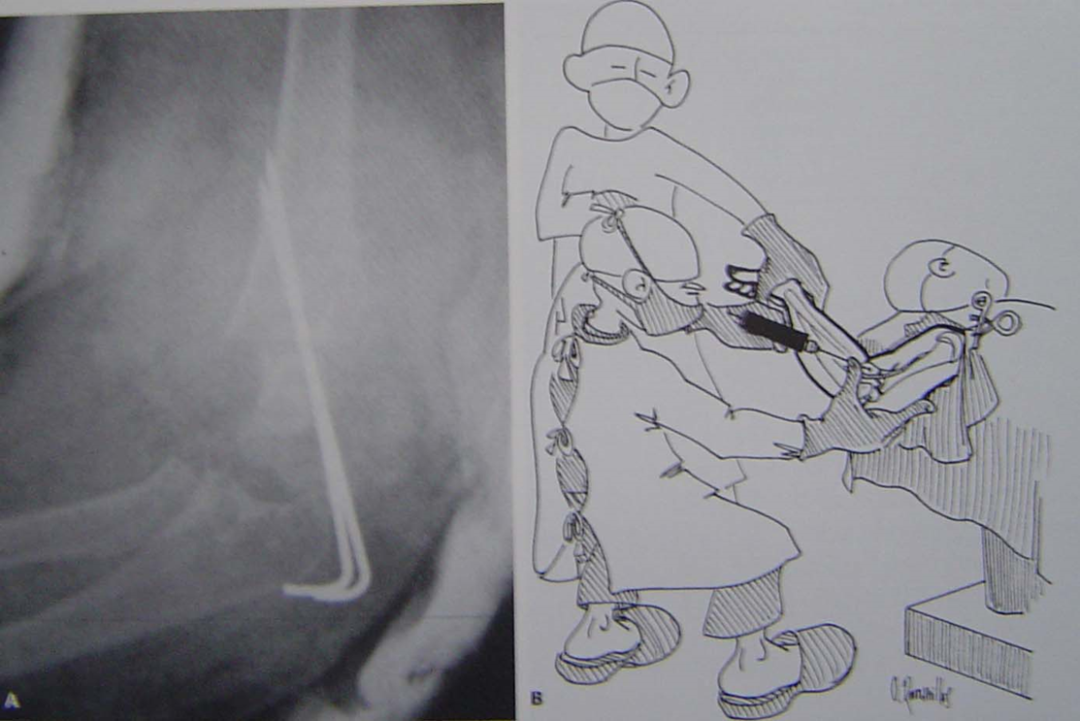

A  患者麻醉后仰卧于手术台边肩关节外展90度c臂x线机在床头牵引腕部,反牵引胸部

B术者一膝跪地,先矫正 侧方移位。拇指顶在鹰咀,余四指环抱肘前牵引下完全屈曲肘关节

C X线透视,AP,L位对位良好,外侧经皮克氏针二根平行或分叉固定

D 透视下外旋肘关节观察稳定性。如果移位,重新复位,内侧第三根克氏针固定